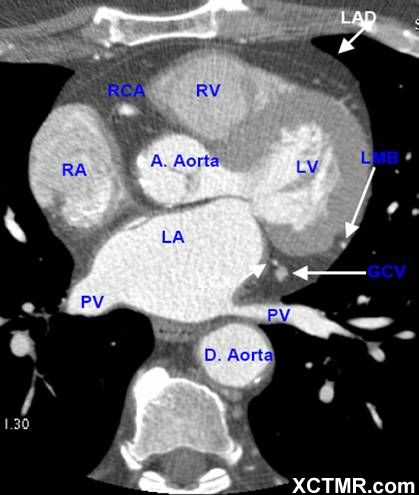

LA - Left Atrium 左心房

RA - Right Atrium 右心房

LV - Left Ventricle 左心室

RV - Right Ventricle 右心室

A. Aorta-Ascending Aorta 升主动脉

D. Aorta-Descending Aorta 降主动脉

PV - Pulmonary Vein 肺静脉

LAD - Left Anterior Descending Artery 左前降支

LMB - Left Obtuse Marginal Branch 左边缘支(钝缘支)

RCA - Right Coronary Artery 右冠状动脉

GCV –Great Cardiac Vein 心大静脉